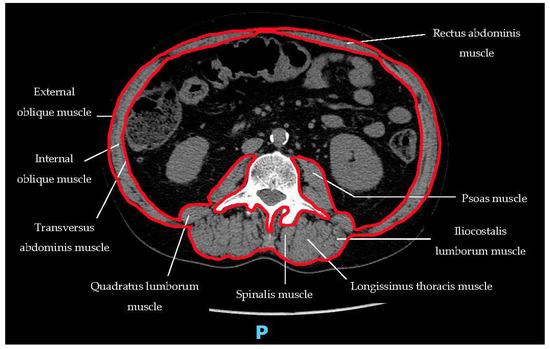

3. Detection of Sarcopenia